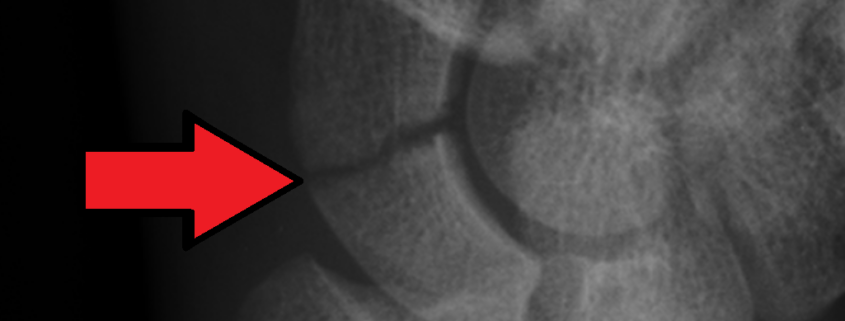

If your doctor suspects a scaphoid fracture, they will usually order an X-ray of your hand and wrist. However, as these types of fractures can be hard to see on X-rays, especially if the X-ray is taken soon after the injury, you may require further imaging such as a CT scan or MRI. A physical exam can also provide clues; tenderness in the “anatomical snuffbox” area of your wrist often suggests a scaphoid fracture.

3. Distal pole: These fractures are towards the thumb, best seen on an X-ray sideways view. They tend to heal well given the good blood supply at this end of the bone.